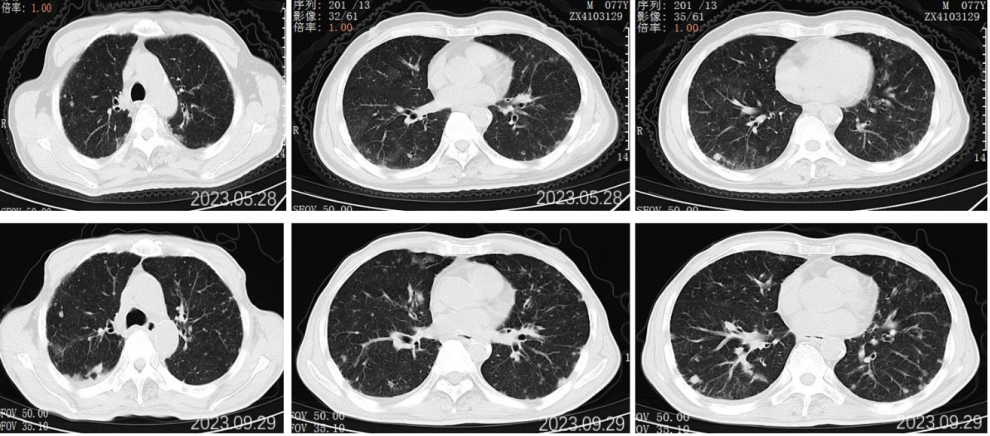

2022.09.27胸部CT平扫:1.两肺多发小结节、类结节影,较前相似,转移性考虑;2.两侧胸腔少量积液较前已吸收。3.左侧第5后肋骨质破坏。

2022.11.25胸部CT平扫:对比2022-09-27影像:1.新见两肺多发间质性肺炎样改变,感染考虑,VP-RADS 2类;2.两肺多发小结节、类结节影,部分较前略缩小,转移性考虑;3.左侧第5后肋骨质破坏,相仿。

2023.5.28胸部CT平扫:对比2022-11-25片:1.两肺散在多发炎症,较前相仿,VP-RADS 2类;2.两肺多发小结节、类结节影,转移瘤考虑,较前相仿;3.左侧第5后肋骨质异常,相仿。男性乳腺发育。

2023.09.29胸部CT平扫:对比2023-05-28片:1.两肺多发小结节、类结节影,较前增多增大,转移瘤考虑。2.两肺散在多发炎症,部分较前吸收;3.左侧第5后肋骨质异常,相仿;4.右侧胸腔少量积液。男性乳腺发育。